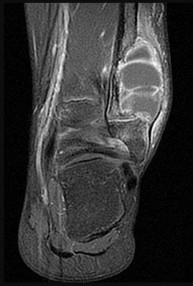

Figures 9a through 9d are the anteroposterior and lateral radiographs, CT scan, and technetium bone scan of a 12-year-old boy who has experienced 7 months of pain in his lower leg. The pain limits his ability to participate in sports and he is having difficulty sleeping. He is afebrile, and laboratory study findings including an erythrocyte sedimentation rate, C-reactive protein, and complete blood count are within normal limits.

The images and clinical history support a diagnosis of osteoid osteoma, which most commonly occurs in adolescence. Although these lesions can be seen in any bone, they are usually located in the femur and tibia. The significant inflammatory response to this tumor is secondary to high levels of prostaglandin production. Characteristic night pain is relieved with nonsteroidal anti-inflammatory drugs (NSAIDs) or by aspirin.

Radiographic images show thickened bone and a small central nidus. Thin-cut CT scan is the imaging of choice to visualize the nidus. A bone scan is associated with uptake but is not specific. Treatment options include expectant management with NSAIDs and observation under the premise that these lesions eventually burn out. Contemporary treatment involves RFA. Historically, these lesions were treated with en bloc resection; however, this technique has largely fallen out of favor because of the high efficacy and comparative low morbidity associated with RFA.

When an osteoid osteoma occurs in the spine, it is located in the posterior elements, and paraspinal pain and scoliosis often are present.